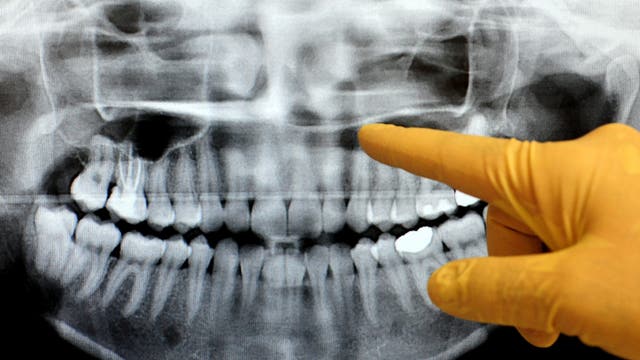

Michigan dentists dropping lead aprons during patient x-rays

New guidance from the American Dental Association last year is recommending changes to how dentists take x-rays of patient's mouths.